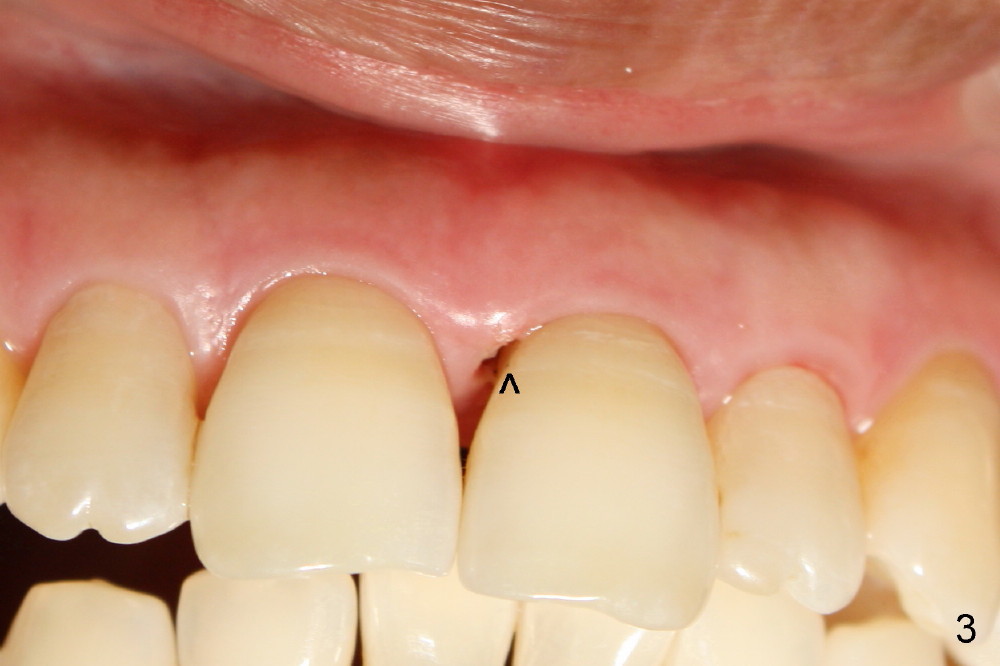

A 60-year-old lady had an abscess mesial to #9 six years ago (Fig.1,2 <), treated as a perio lesion by laser (Fig.3) and osseous surgery without bone graft (Fig.6, followed by CT exam revealing semi-circumferential bone loss (Fig.4,5). When the perio treatment failed, attention was paid to endo aspect (Fig.7-9). In fact the pulp was found to be vital when access to root canal therapy was made. As expected, the treatment failed again. The palatal fistula persisted. The infection was suspected to be a source of remote immediate implant site (#30). The tooth #9 was extracted. It appears that there is a semilunar crack line in the linguomesial root (Fig.12). When the socket healed 2 weeks post extraction (Fig.10), the #30 buccal defect was debrided with bone graft. There was no bone resorption 4 weeks post extraction (Fig.11); a 4.5x17 mm implant was placed (Fig.13-15). An immediate provisional was fabricated (Fig.16-18). Fig.19,20 were taken 3 months post implantation and 7 months post cementation, respectively. Dense bone forms around the implant coronally 4 years 5 months post cementation (Fig.21), while the gingiva is healthy palatally (Fig.22) and buccally (Fig.23).